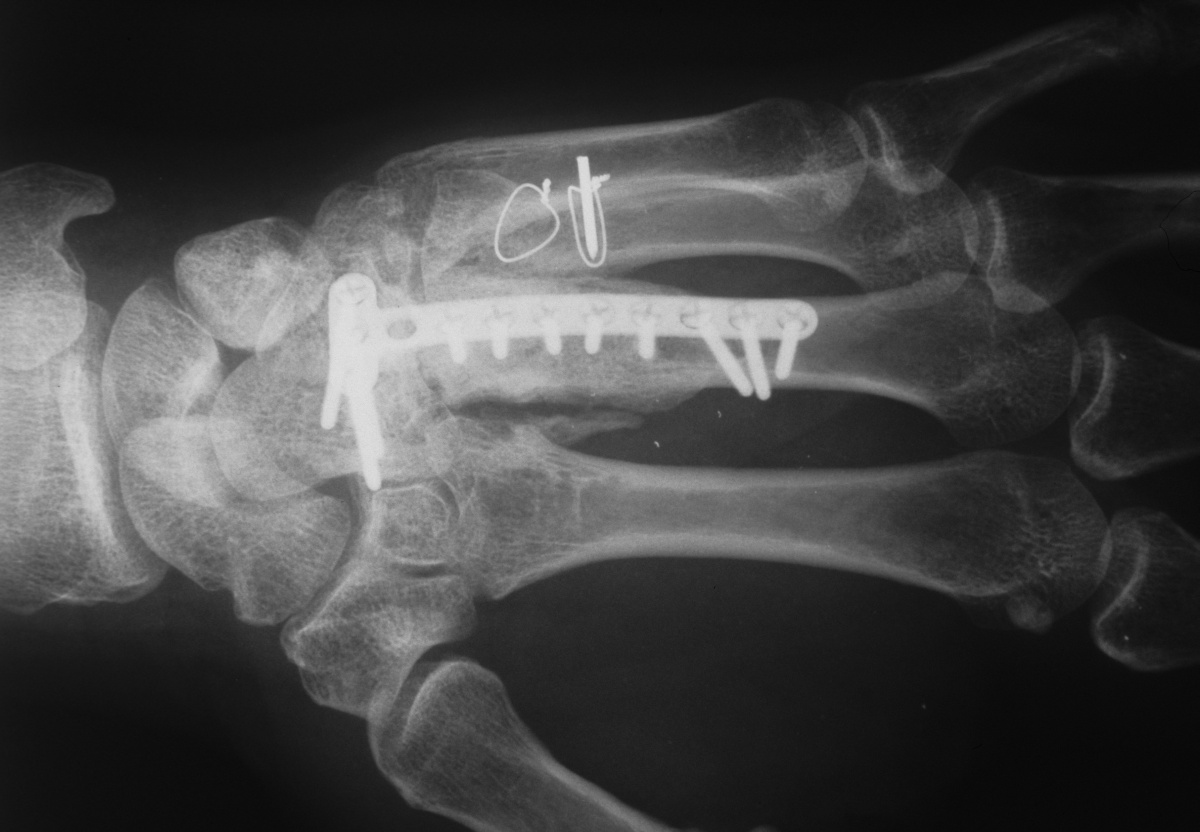

| Fixation of

bicortical iliac crest graft incorporating

carpometacarpal arthrodesis. |